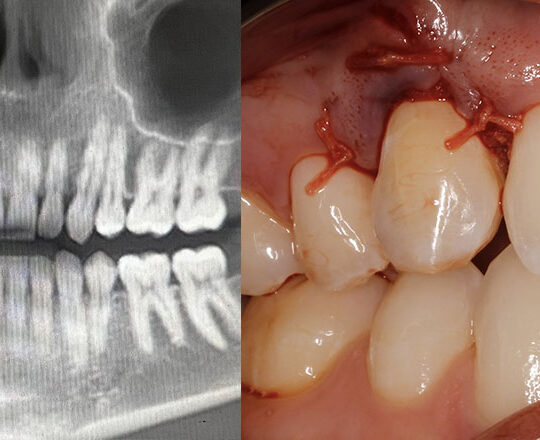

Real Case Applications

Content grounded in actual clinical scenarios and outcomes.

Stay sharp and up to date. Dive deep into real-world cases and techniques guided by expert instructors, and bring back practical skills to your practice.